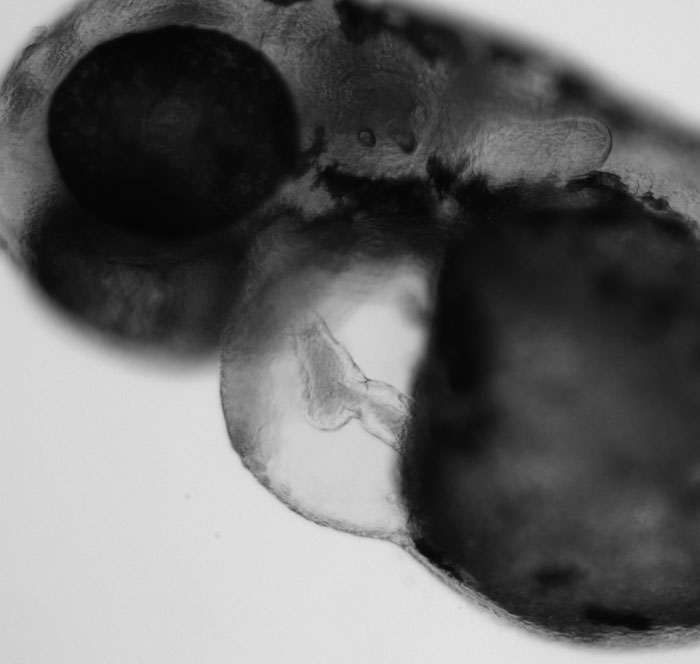

Steroids acting at the cell membrane

Steroids, like estrogens and androgens, are small molecules that can slip through the cell membrane and bind to receptors inside the cell’s cytoplasm and nucleus. In 2005, several labs discovered that estrogens can bind to a protein in the cell’s plasma membrane, meaning that steroids can activate receptors on the outside of a cell, without having to enter the cell. We are fascinated by this non-canonical signaling pathway and seek to understand the biological functions of membrane-associated steroid hormone signaling. We discovered that estrogen signaling at the cell membrane increases heart rate in embryos, but has no effect on the development of the gonad. We are also interested in how membrane-associated androgen and progestin signaling influences embryonic development and organ formation.